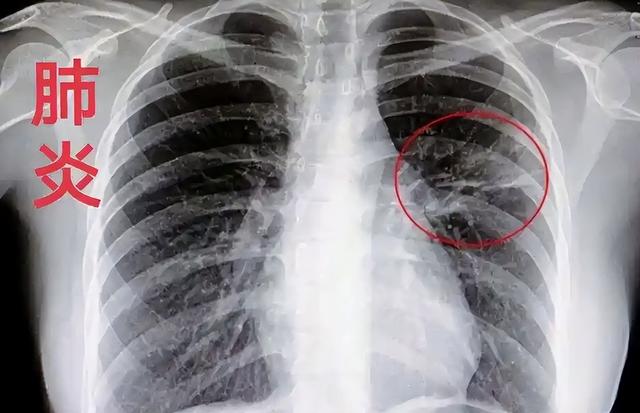

甲型流感病毒,简称甲流,是一种高度传染性的呼吸道病毒感染,与普通感冒不同,它更具爆发性和系统性,严重时甚至可引发肺炎、心肌炎等并发症,个别重症患者可能因多器官功能衰竭而死亡。

甲流病毒分为多个亚型,其中H1N1、H3N2是主要流行株。病毒通过空气飞沫、接触传播,传播速度快、潜伏期短,尤其在学校、地铁、办公室这样人群密集的场所,极易造成聚集性传播。

典型症状包括高烧、肌肉酸痛、剧烈乏力、咳嗽等,比起普通感冒来得更猛。